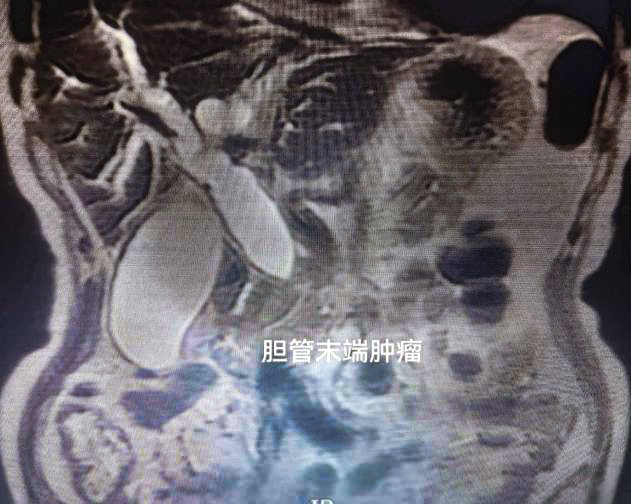

肝胆外科副主任周新红接诊后,敏锐判断病情危重,立即安排上腹部增强CT及磁共振检查。结果显示,患者胆总管下段及胰腺段存在肿瘤性病变,已导致胆道严重梗阻。